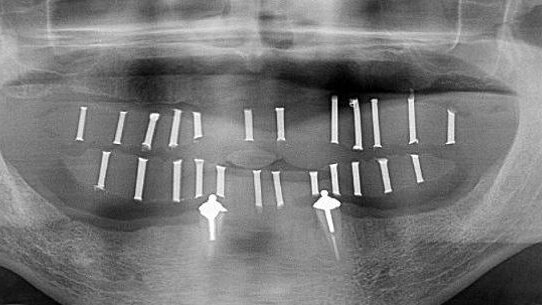

Implantology

With increased demand for replacing missing teeth with dental implants, accurate measurements are needed to avoid damage to vital structures. This was achievable with conventional CT. However, with CBCT giving more accurate measurements at lower dosages, it is the preferred option in implant dentistry today (Figs. 4a & b).2,6,11,18,70,77–89

CBCT enables the assessment of bone quality and bone quantity.18,26,70,80–81,85,88,95–97 This leads to reduced implant failure, as case selection can be based on much more reliable information. This advantage is also used for post-treatment evaluation and to assess the success of bone grafts (Figs. 5a–d).18,88

The literature on CBCT is promising and needs further research, especially with regard to its use in forensic dentistry, in order to explore more potentially beneficial indications in that area. No literature concerning direct CBCT indications in prosthodontics was found. However, several overlapping indications were found in other dental specialties attributing to the final standard of care in prosthodontic treatment. These indications include but are not limited to bone grafting, soft-tissue grafting, prosthetically driven implant placement, maxillofacial prosthodontics and temporomandibular joint disorder. CBCT images can also be of great value in special cases in which multiple teeth have to be assessed for restorability (Figs. 7a–e).